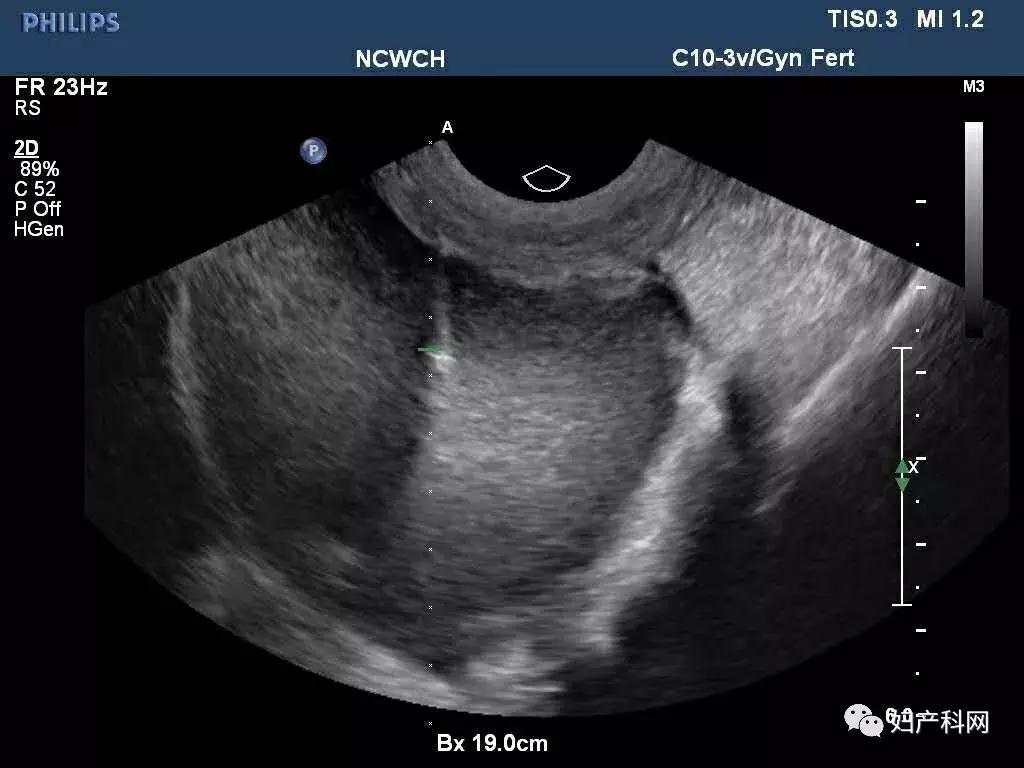

超声提示:右侧卵巢囊肿大小约7.4×4.7cm,巧囊不除外,ca125 37.7u/ml,HE4 40.6pmol/L。

术中超声

我们给这位患者选择的是经阴道卵巢囊肿穿刺+无水酒精固化,术中见右侧卵巢囊肿分为2房,分别从2房中抽出了约100ml巧克力样粘稠液体,共计200ml,每个房分别注入了50ml的无水酒精固化15分钟后抽出,术中同时放置了一枚曼月乐。

前几天这位患者再次来我们门诊复查,之前因为卵巢囊肿过大,超声甚至很难找到右侧正常卵巢策划,这一次可以轻松的发现了,囊肿也没有复发,当然后续还需要进行持续的随访。